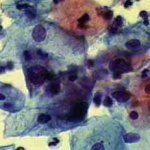

Δυσπλασίες τραχήλου μήτρας σοβαρού βαθμού (CIN III)

Ασυμπτωματική ασθενής 39 ετών. PH κόλπου 4,4. Κολποσκόπιση:

Στην δοκιμασία οξικού οξέως και στην δοκιμασία Lugol, αρνητική περιοχή, τόσο στο πρόσθιο, όσο και στο οπίσθιο χείλος του τραχήλου, σε ακτίνα 3-4 χιλ. και πλάτος περίπου 5 χιλ., με εικόνα διακριτικού επίπεδου μωσαϊκού.